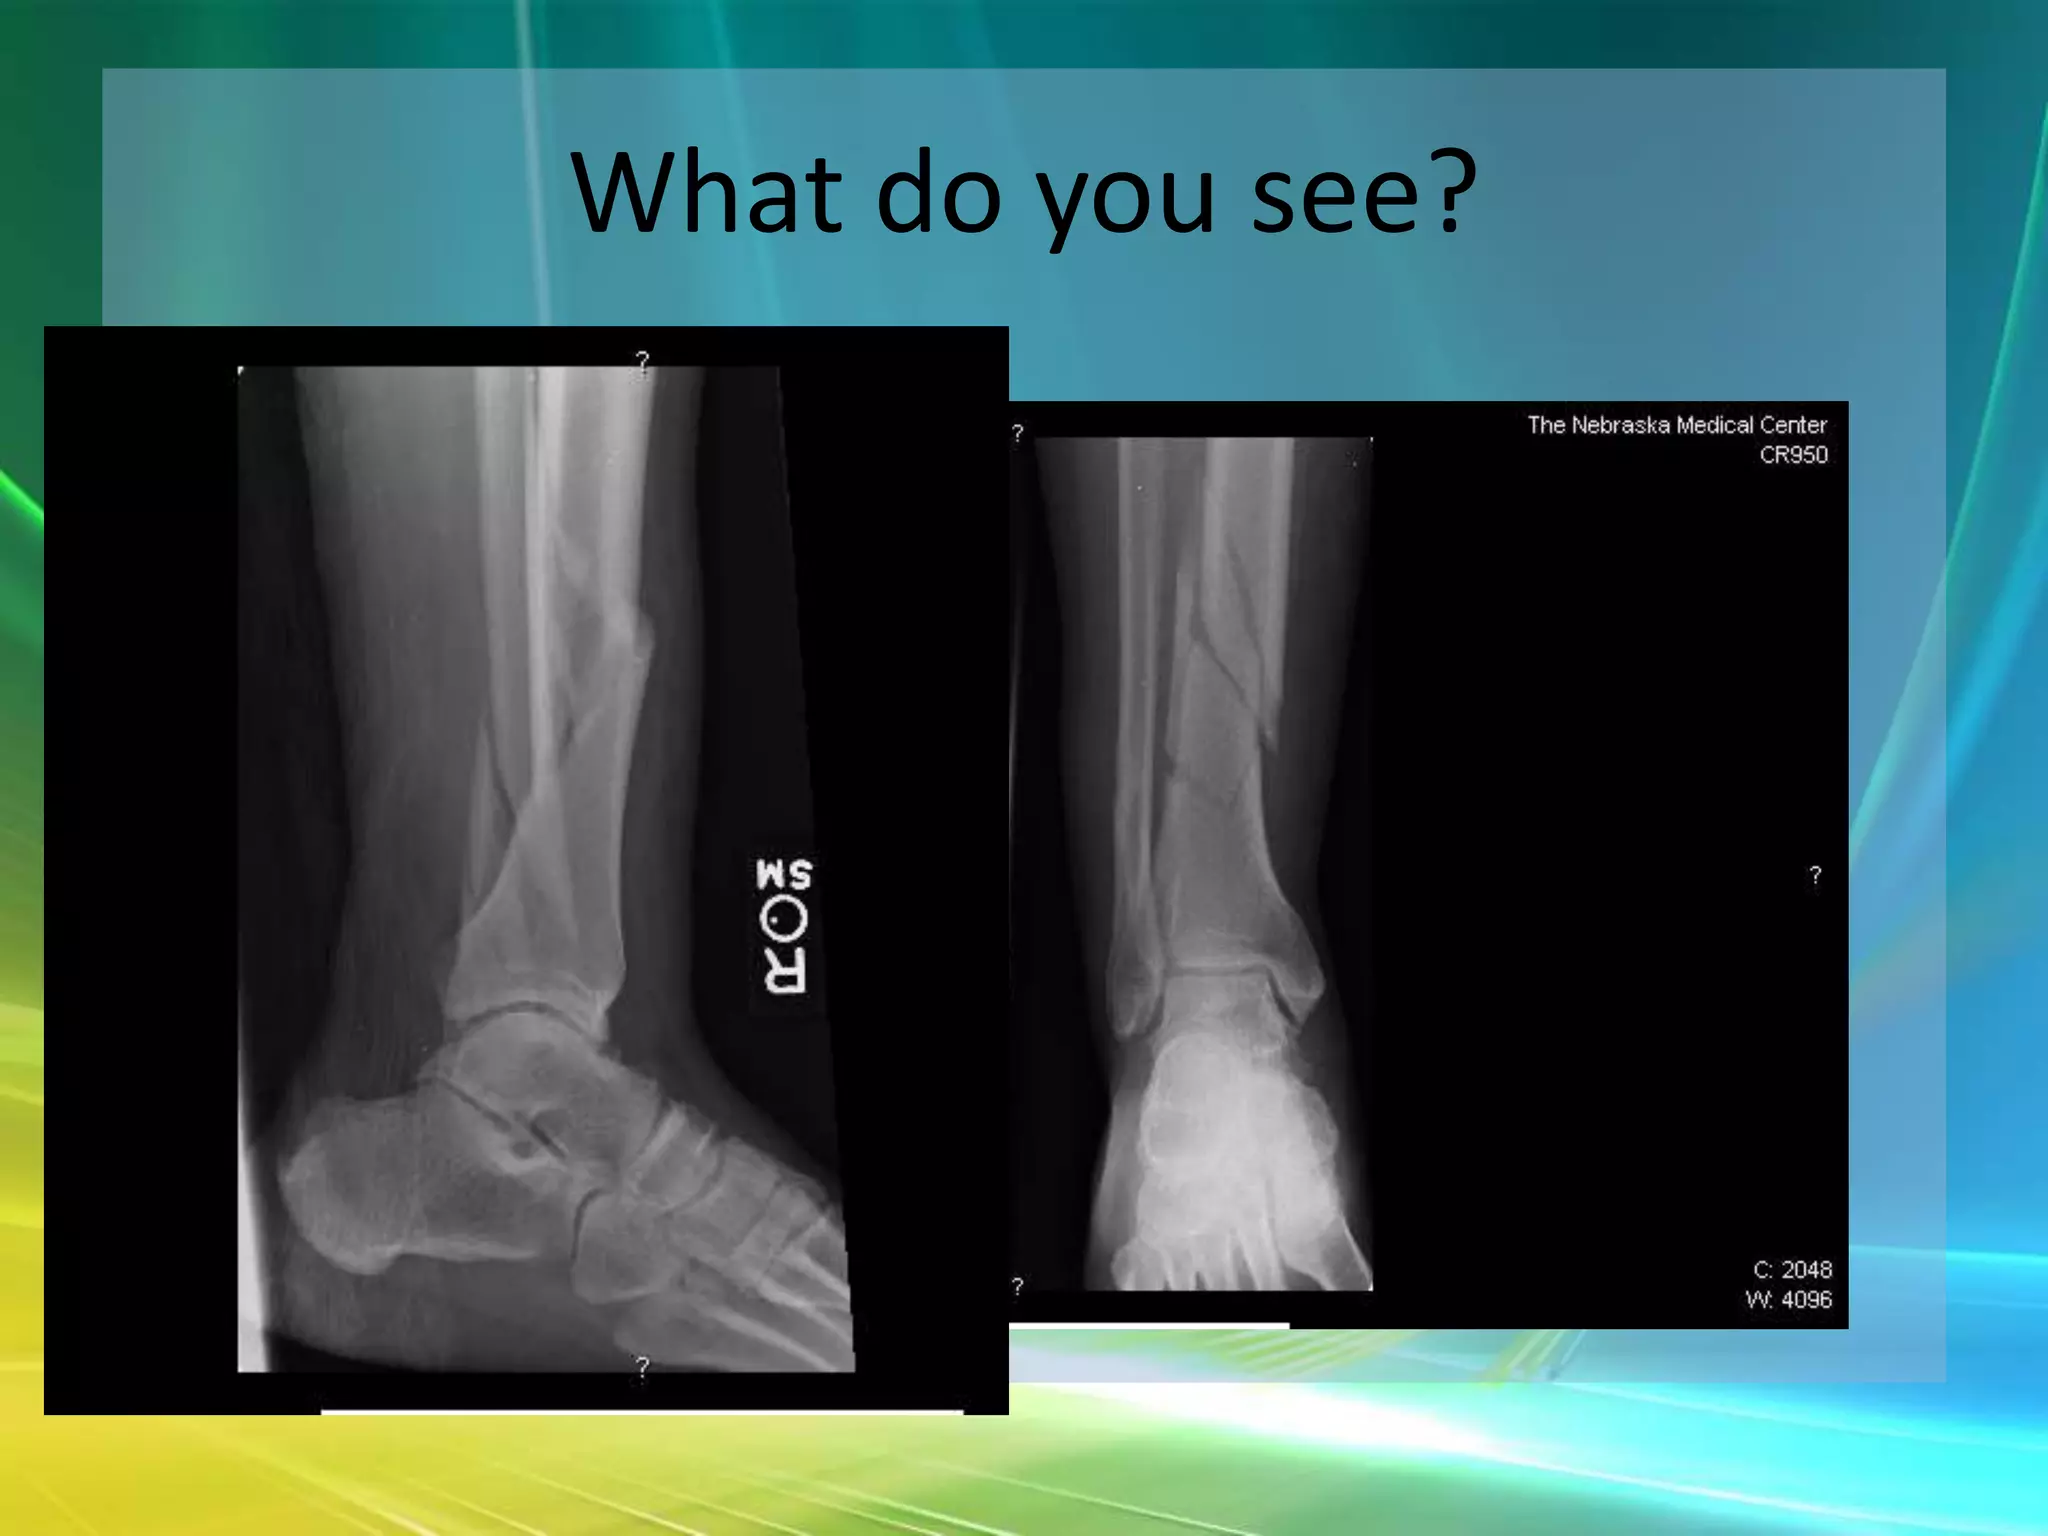

What do you see?